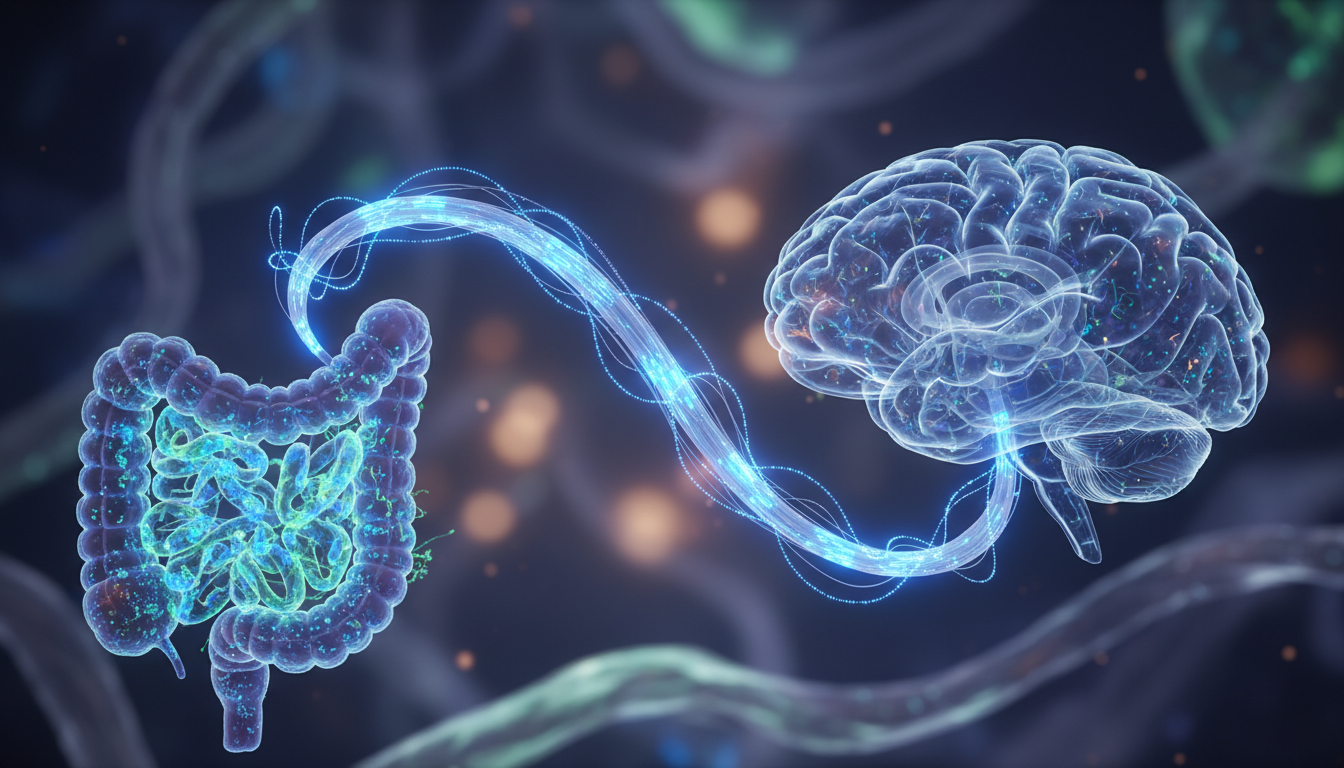

La Autopista de la Información: El Nervio Vago

El eje intestino-cerebro es una línea de comunicación bidireccional física y química. El nervio vago es el cable de fibra óptica que conecta estos dos órganos. Cuando tu microbiota está en disbiosis (desequilibrio), las bacterias patógenas liberan lipopolisacáridos (LPS) que atraviesan la barrera intestinal. Esto activa una respuesta inmune sistémica, enviando citoquinas inflamatorias directamente al cerebro.

El resultado clínico es lo que llamamos «comportamiento de enfermedad»: letargo, anhedonia y ansiedad. Si no entiendes el vínculo entre el estrés mental y tu dolor físico crónico, seguirás tratando los síntomas con analgésicos mientras la causa raíz sigue inflamando tu sistema límbico desde el estómago.